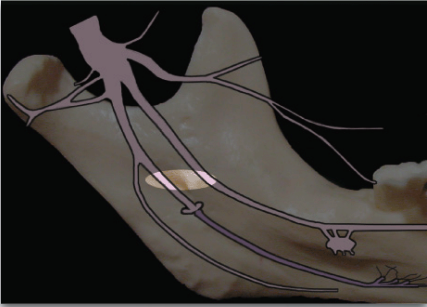

mylohyoid nerve can provide portion of pulpal innervation to which mandibular teeth?

most commonly in the mesial portion of the mandibular 1st molar or premolars

______ nerve block can be a useful supplement to inferior alveolar block when it appears to be inadequate

Mylohyoid

what is the proper technique for mylohyoid nerve block?

Use 25 gauge long needle

Retract the tongue

Direct the syringe from the opposite side

Direct needle tip to the apical region of the tooth immediately posterior to the tooth in question, until bone is contacted

Aspirate and deposit ~0.6 ml of solution